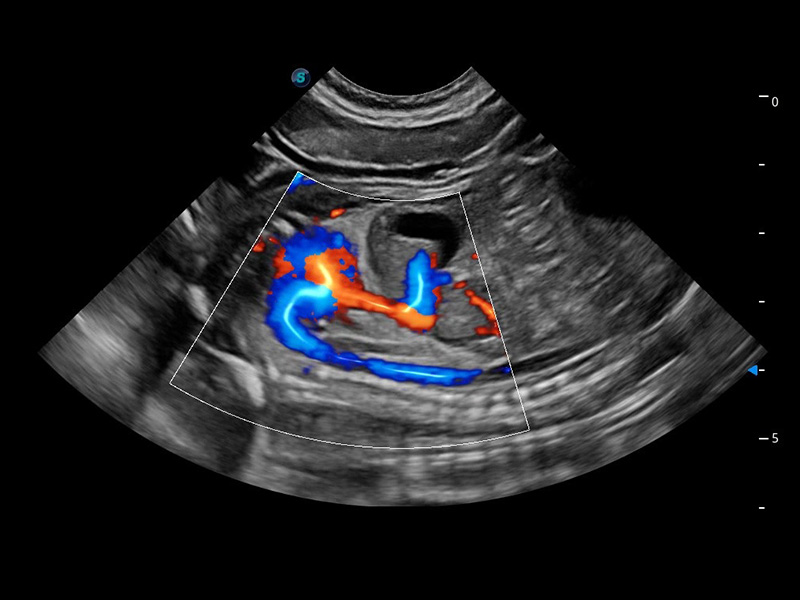

ProPet 60 作为一款高端台式动物超声设备,为动物医生的日常诊断提供了一系列贴合动物临床需求、解决临床实际问题的高级成像功能。凭借全系列高清探头,满足医生对腹部、心脏、生殖、浅表、肌骨等成像的所有需求,切实帮助您提升检查效率,提高诊断信心。

兽用彩色多普勒超声诊断系统

动物是人类最亲密的朋友和最值得信赖的伙伴。DB中国旗舰官方网站也一直致力于探索动物专用的超声影像解决方案。 全新推出的ProPet系列,是DB中国旗舰官方网站在动物超声影像智能化、专业化、精准化的一次跨越式革新。动物不能用言语来表述自己的不适,通过超声影像,ProPet系列搭建了动物医生与不同物种沟通的“桥梁”,为动物医生注入了“治愈之力”。